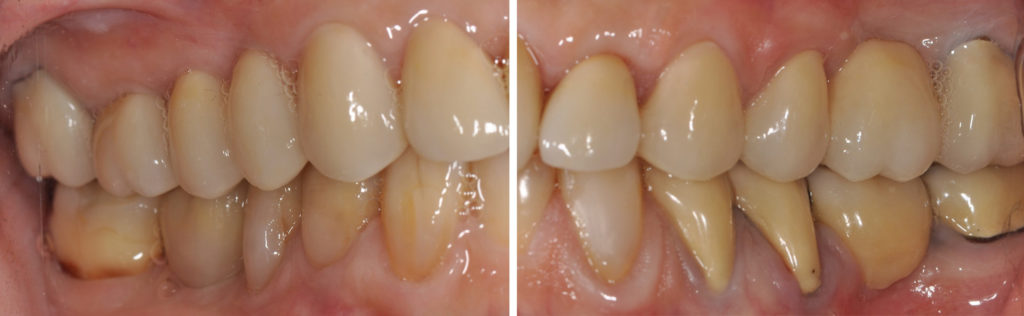

Fig. 8a à 8j : Résultat final

Un soin tout particulier doit être apporté à l’équilibration occlusale. L’équilibre occlusal est assuré, en OIM, par des contacts bilatéraux, simultanés et d’égale intensité sur les dents postérieures de canines à deuxièmes molaires (Fig. 9a et 9b). Les rapports inter-incisifs en OIM doivent laisser échapper une feuille de 9 microns d’épaisseur (Fig. 9c). Les entrées et sorties de cycle masticatoires sont contrôlés par élimination des interférences entre les versants cuspidiens des dents postérieures d’une part, et des faces palatines des incisives maxillaires et les bords libres des incisives mandibulaires d’autre part.

AVANT/APRÈS :